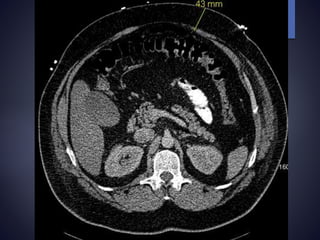

Parastomal hernia

 Abdominal CT scan helpful in c/o difficulty

How are wegoing to get this through that ?

Skin Fascia 9 cm 9cm +2cm = 11cm of Sigmoid Colon 9cm + 6cm = 15cm of Terminal ileum BMI 48.7